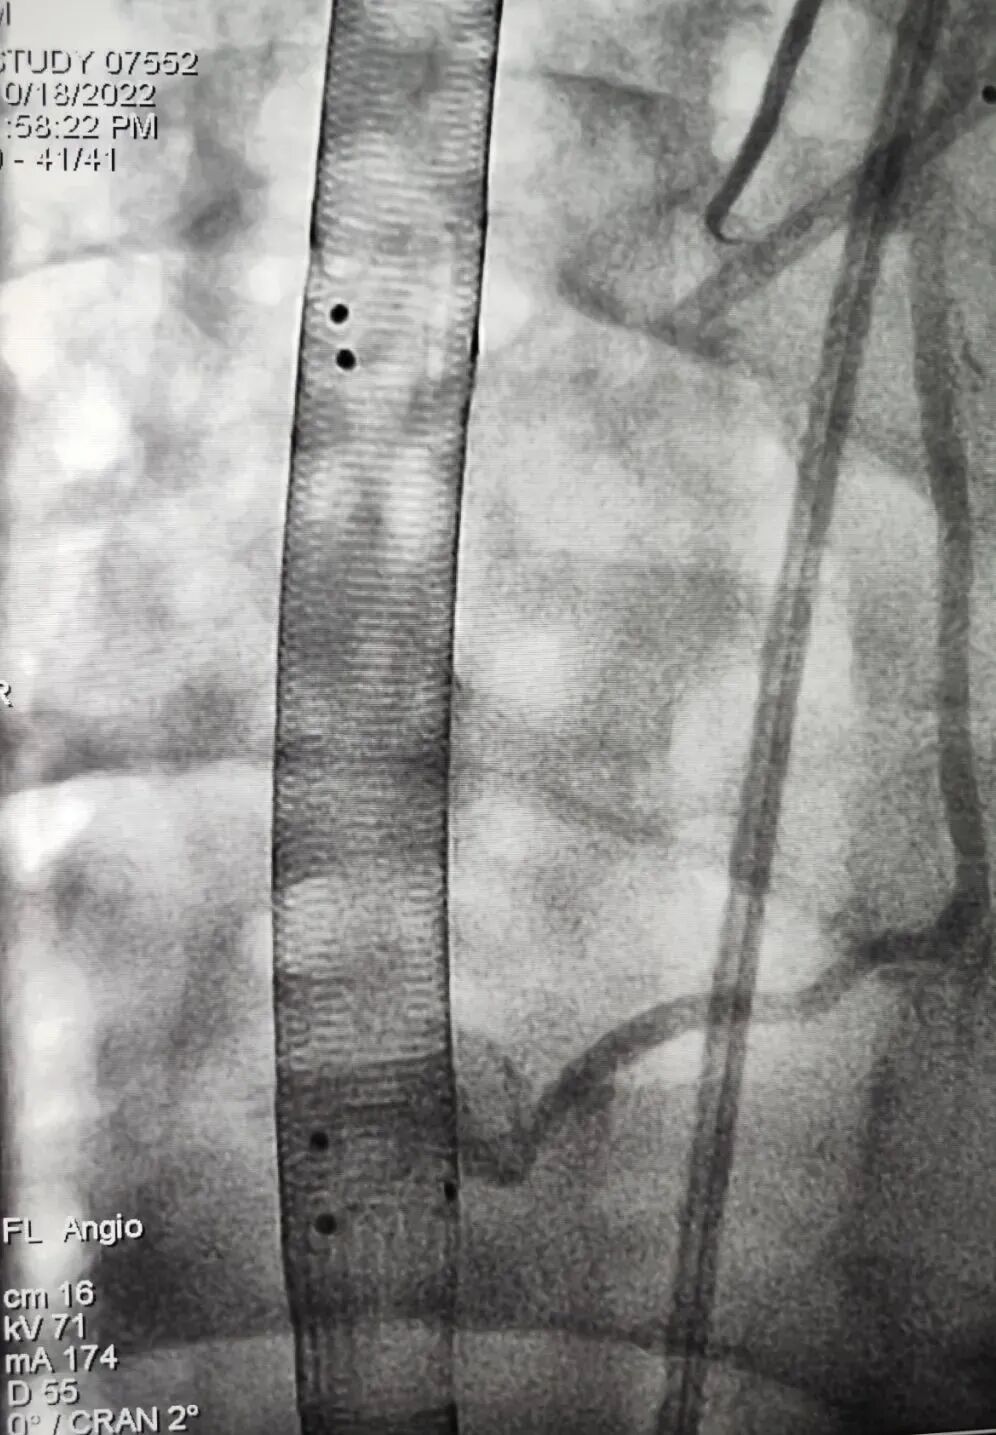

X射线下快速实现Crescent定位

Crescent双腔颈静脉ECMO插管通过创新的设计(在插管重要的引流和灌注部位设置的不透射线标记),使得除超声引导置管外,也可在X射线下(如DSA,床旁X光机等)进行置管及日常的定位操作;为临床快速判断插管位置提供更多便利与可能!

Crescent 双腔插管的不透射线标记

DSA清晰显示Crescent标记点

指示双腔插管位置